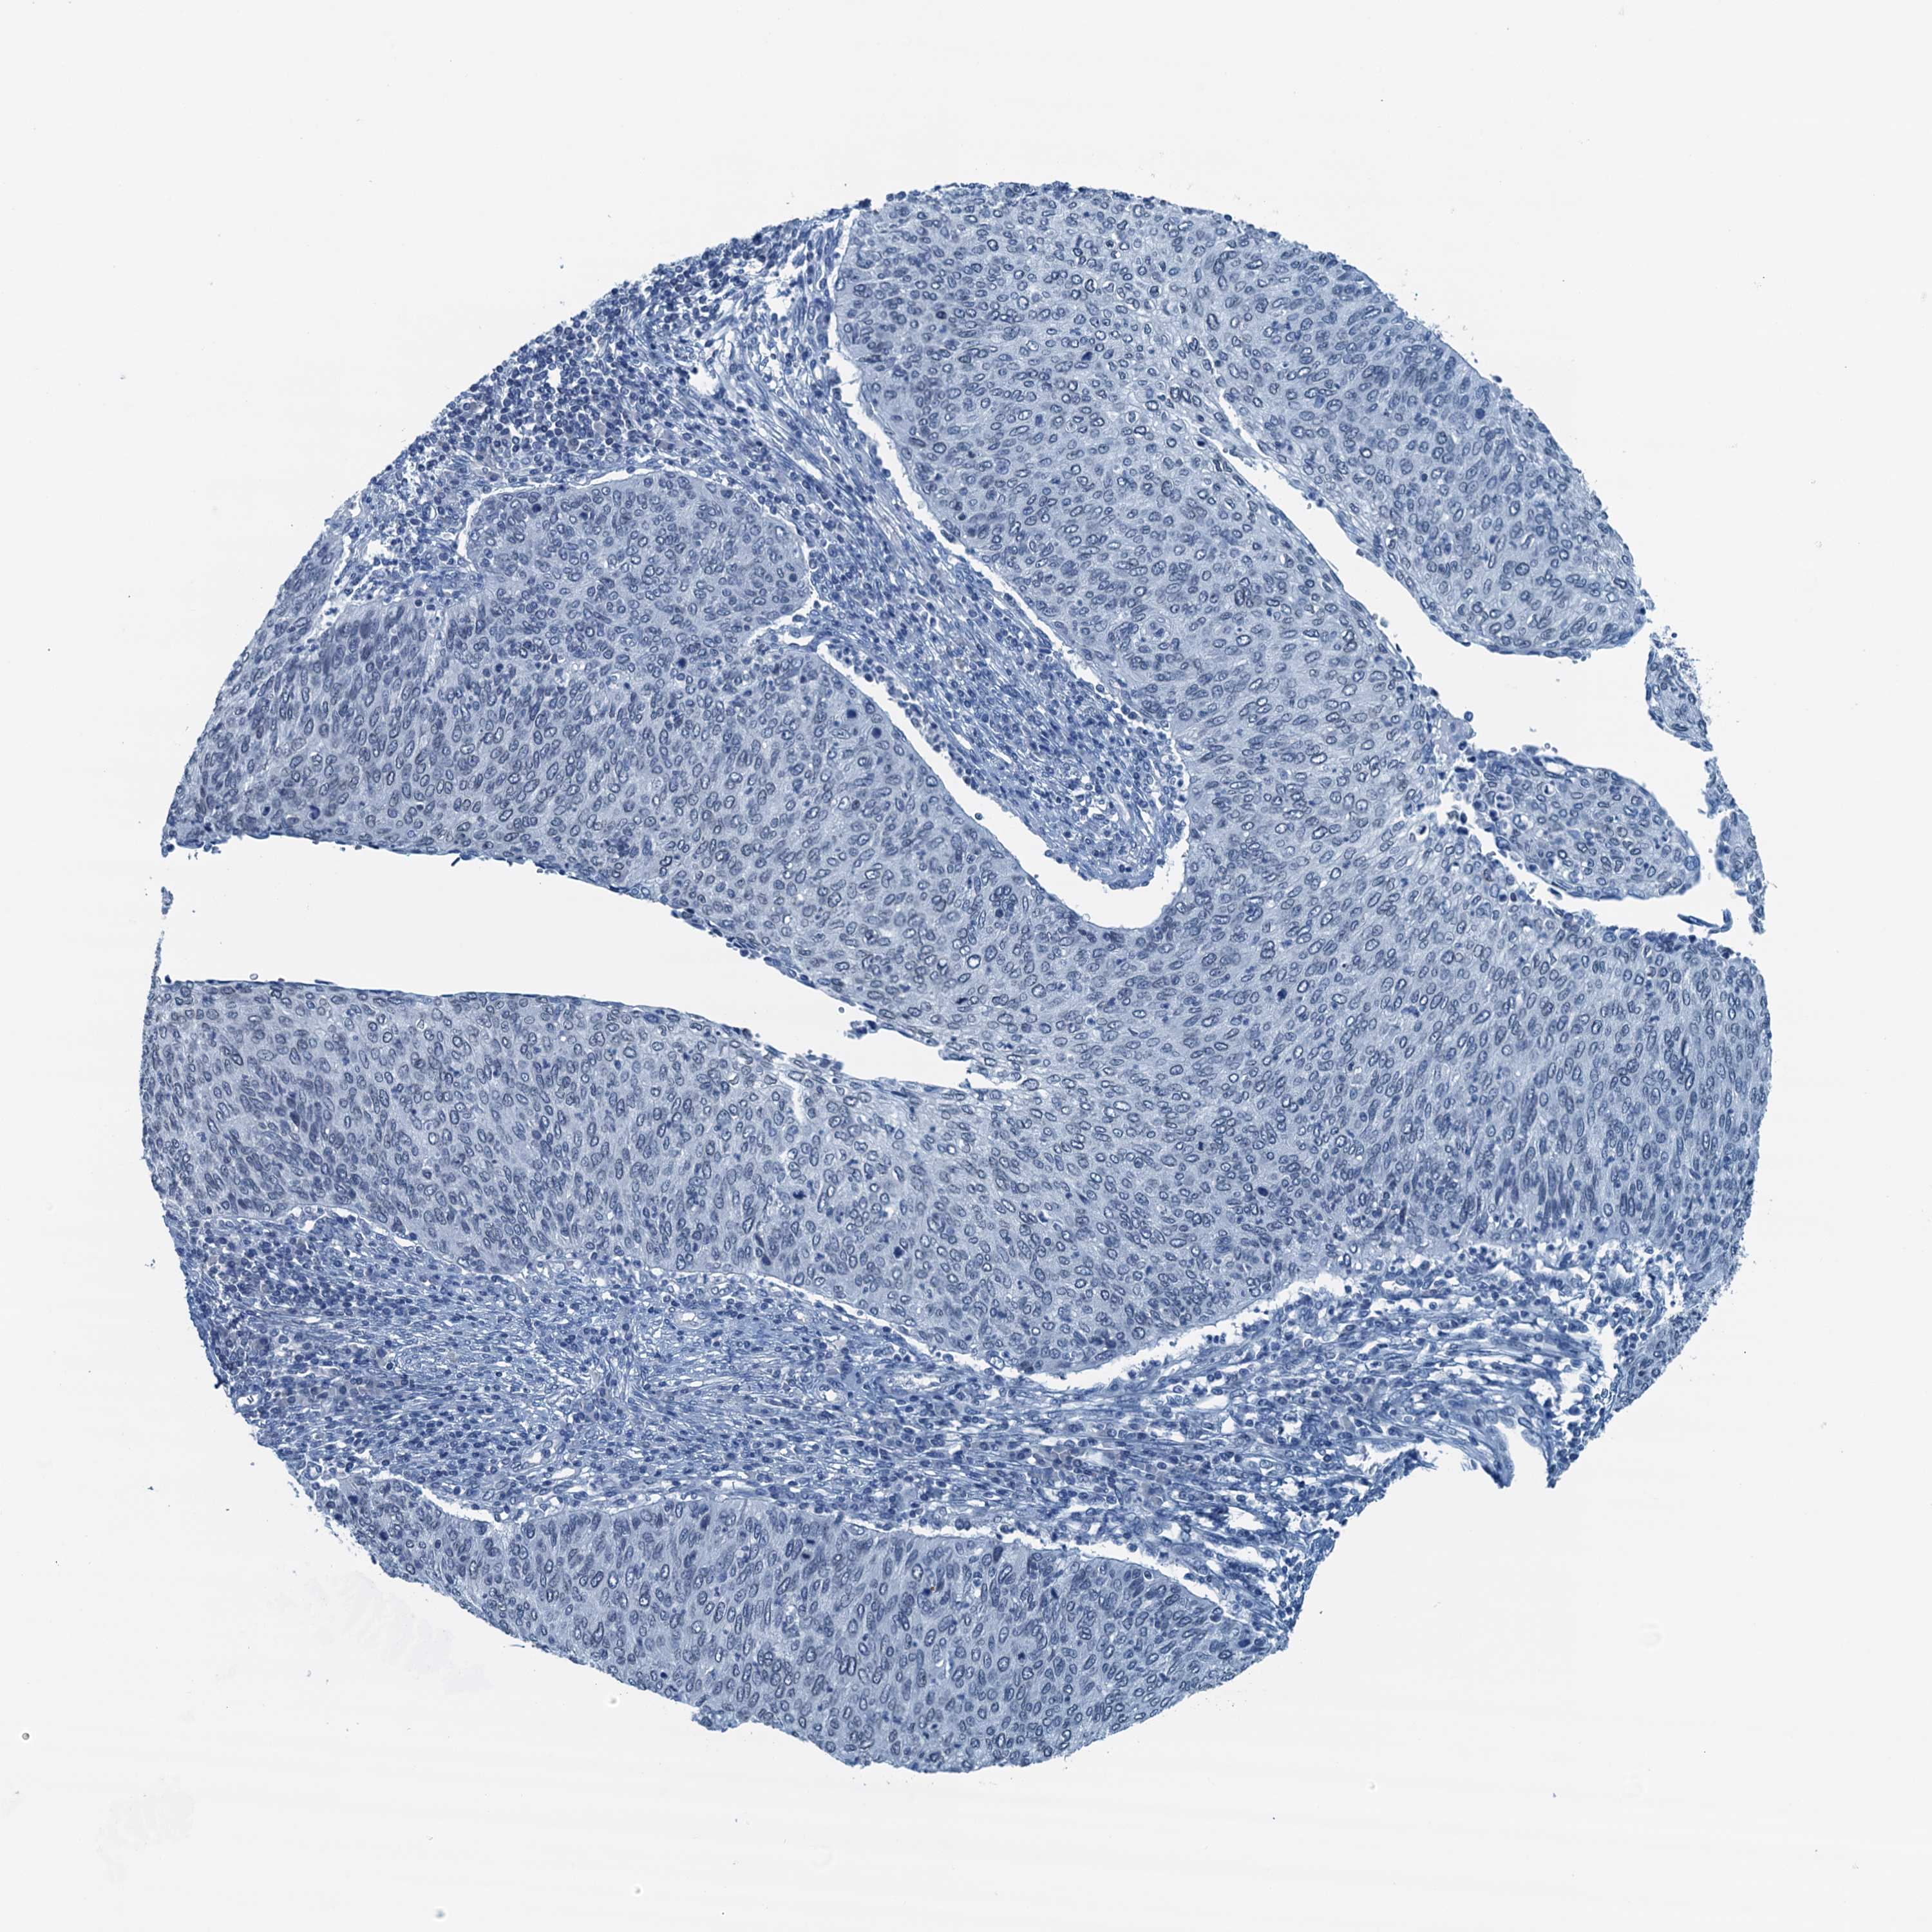

CERVICAL CANCER - Protein expressioni

A mouse-over function shows sample information and annotation data. Click on an image to view it in a full screen mode. Samples can be filtered based on level of antibody staining by selecting one or several of the following categories: high, medium, low and not detected. The assay and annotation is described here.

Note that samples used for immunohistochemistry by the Human Protein Atlas do not correspond to samples in the TCGA dataset.

Antibody stainingi

Antibody staining in the annotated cell types in the current human tissue is reported as not detected, low, medium, or high, based on conventional immunohistochemistry profiling in selected tissues. This score is based on the combination of the staining intensity and fraction of stained cells.

Each image is clickable and will lead to virtual microscopy that enables deeper exploration of all samples and also displays staining intensity scores, fraction scores and subcellular localization as well as patient and tissue information for each sample.

Antibody HPA040511

Staining

High

Medium

Low

Not detected

Intensity

Strong

Moderate

Weak

Negative

Quantity

>75%

75%-25%

<25%

None

Location

Nuclear

Cytoplasmic/membranous

Cytoplasmic/membranous,nuclear

Squamous cell carcinoma, NOS

Adenocarcinoma, NOS